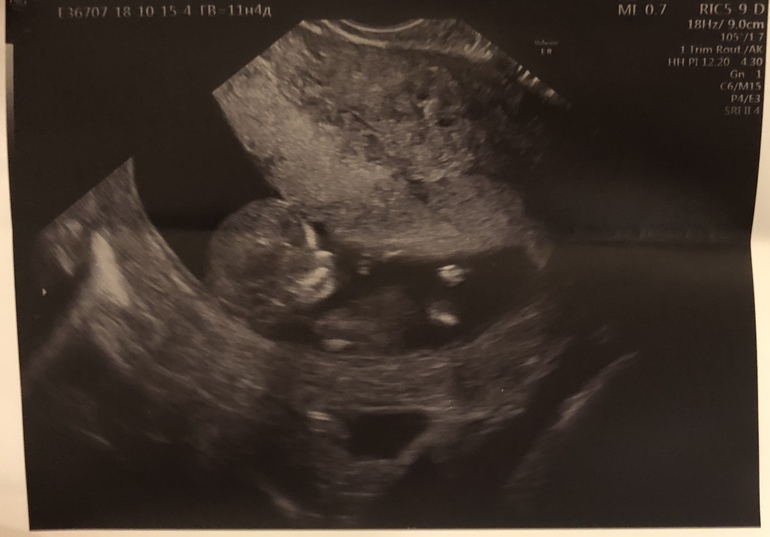

Стоял рядом, за руку меня не держал, романтичной атмосферы не получилось, в общем) Включила она большой экран напротив нас, показала: «Вот голова и профиль, нос, верхняя и нижняя челюсти. Вот ручки согнуты к лицу. Вот сердце пульсирует в грудной клетке. Вот правая нога, а вон левая, видите? Обе согнуты. По УЗИ всё хорошо». Я почти прослезилась от умиления... Муж поугукал и вышел.

Цифры:

Срок - 11 недель 4 дня

КТР - 54 мм

ЧСС - 151 уд/мин

БПР - 16 мм

ТВП - 1,1 мм

Кости носа визуализируются

А вот и фото Кроша 😊